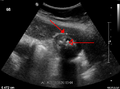

Mild gallbladder wall thickening of 3.5 mm in a person with acute cholecystitis as seen on ultrasound